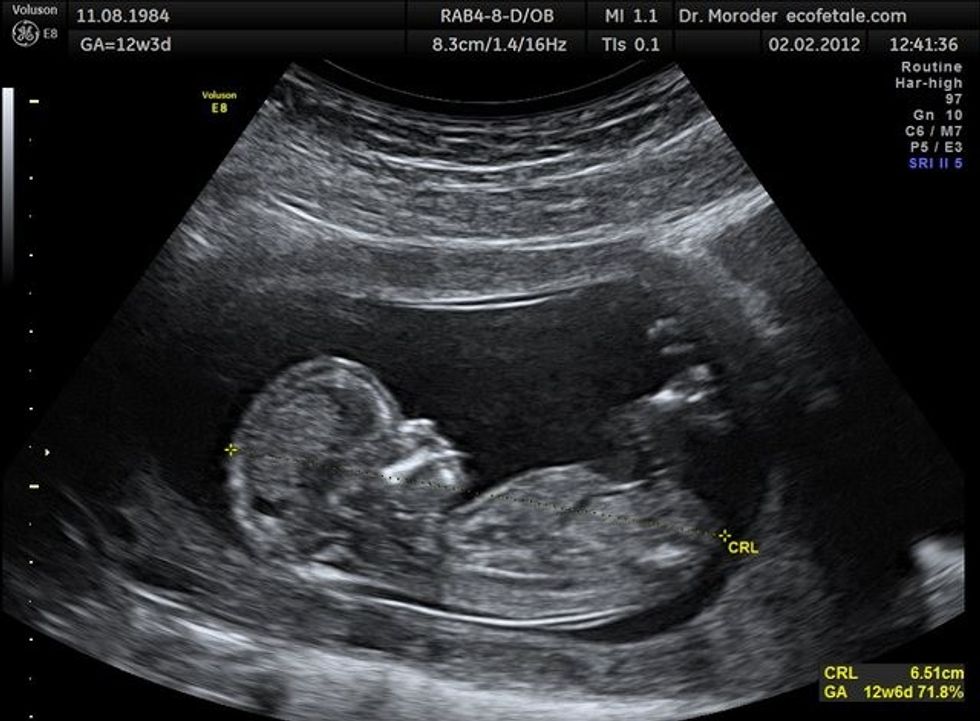

S'ka më dilema: Ç'ndodh me beben kur bën seks në shtatzëni?

Ndoshta seksi është gjëja e fundit që të vjen ndërmend kur je shtatzënë. Por kjo varet nga hormonet, ndaj nëse ke dëshirë të kryesh marrëdhënie dhe je shtatzënë, nuk ka asgjë të keqe, përkundrazi

Dhe si përfundim, bebja nuk i ndjen “gudulisjet” gjatë seksit. Penisi godet cerviksin, i cili shërben si një barrierë për çfarëdo mund të përpiqet të hyjë brenda.

Përveç cerviksit, lëngu amniotik e rrethon beben si një mburojë prej uji, që gjithashtu e mbron beben.